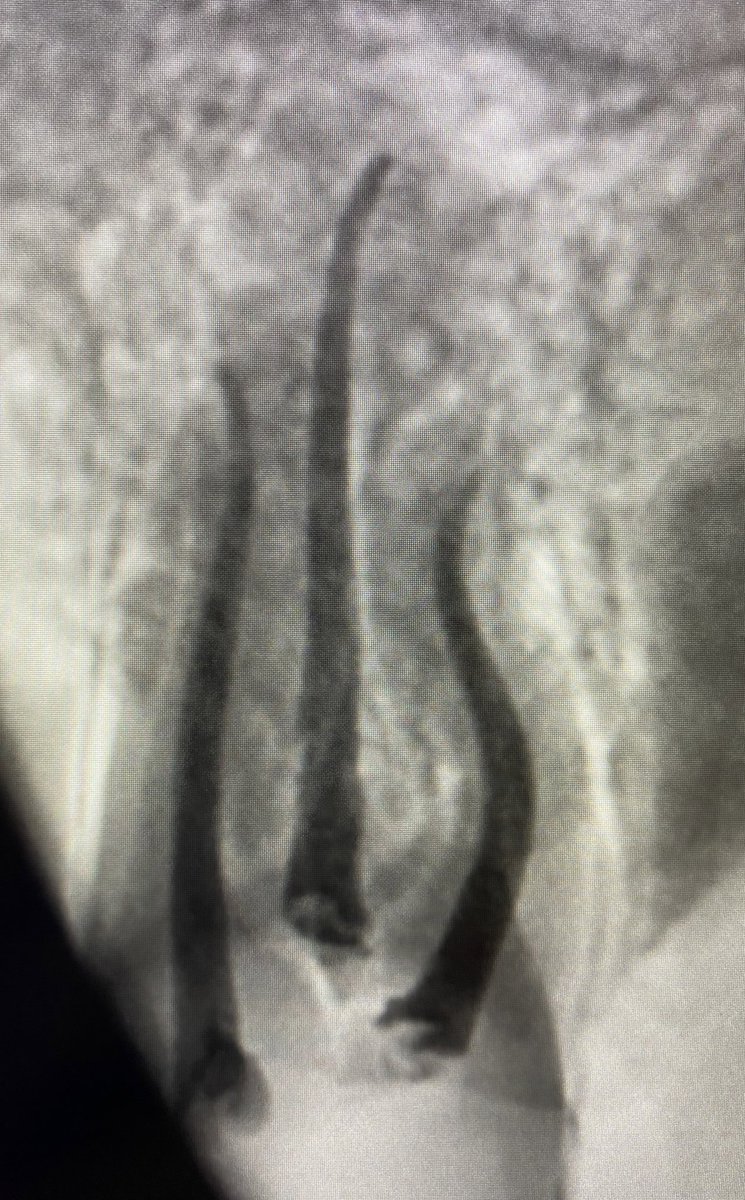

الضرس الثاني للمريض نخللللع ؟

حضر المريض بضرسين مقرره للخلع من كذا عياده وابلغته انه طبعا بالامكان المحافظه عليه وتم ذلك في جلسه واحده

هنا يوجد. Large PA lesion